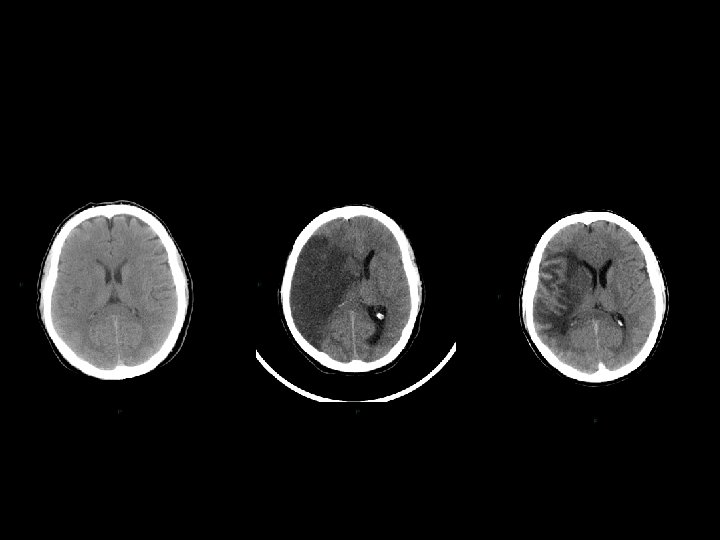

Stato vegetativo • giace, apparentemente incosciente, anche ad occhi aperti; • presenta funzioni cardiocircolatorie e respiratorie, termoregolazione, funzioni renali e gastrointestinali conservate; • non necessita di tecnologie di supporto; • mostra, alla TC e alla RMN, segni più o meno marcati di danno focale o diffuso; • presenta alla SPECT gradi variabili di riduzione sovratentoriali di perfusione cerebrale; • evidenzia, alla PET, variabile topografia e gradi variabili di riduzione del metabolismo del glucosio; • mostra alterazioni variabili dell’attività EEG.